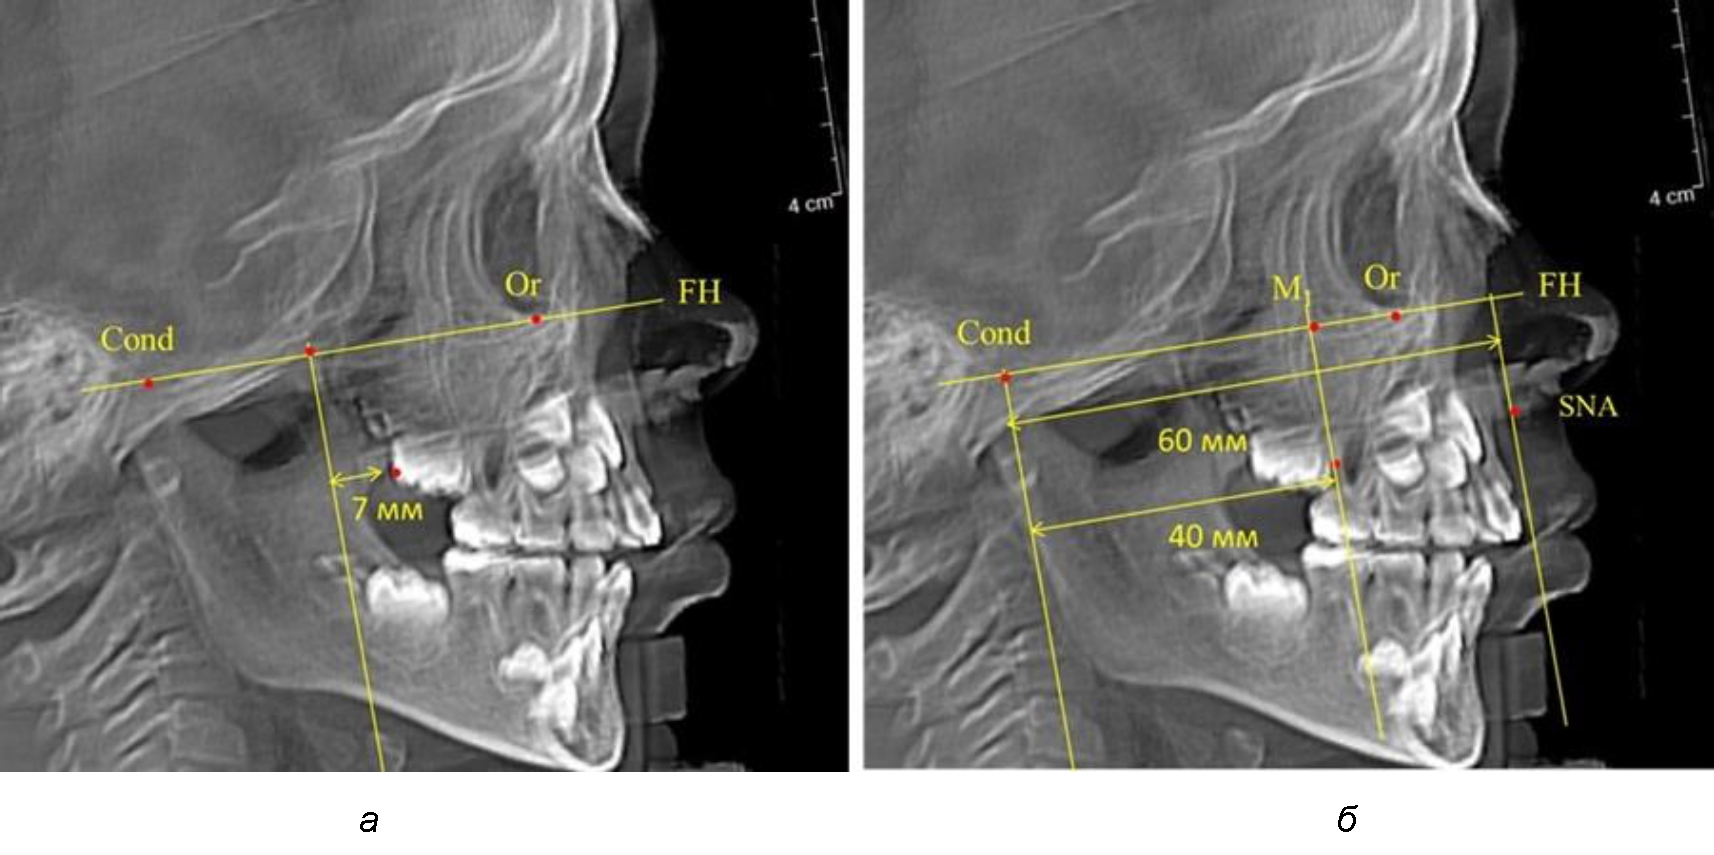

В то же время при увеличенном расстоянии от крыловидной вертикальной плоскости PTV до дистальной поверхности верхнего первого постоянного моляра, равное 23 мм, сагиттальный размер гнатического отдела составил 92 мм. При этом отношение кондилярно-спинального расстояния к кондилярно-молярному размеру (30,5), так же, как и при малых размерах, было близким к коэффициенту 1,5, что представлено на рис. 3.

Рис. 3. Особенности положения первых моляров по R. E. McDonald (а) и по предложенному методу (б) при увеличенном молярно-крыловидном расстоянии